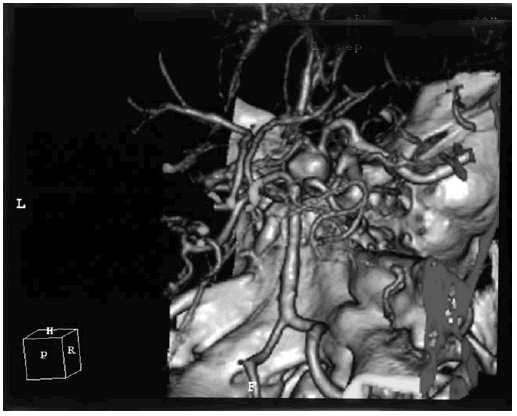

Наличие артериовенозной мальформации левой лобной доли у пациента молодого возраста сопровождалось возникновением УКР и картиной симптоматической эпилепсии (рис. 6.3).

Иллюстрация к книге — Деменция. Диагностика и лечение [i_006.jpg]

Рис. 6.3. Артериовенозная мальформация левой лобной доли у пациента молодого возраста с УКР